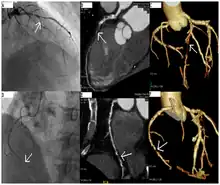

A coronary catheterization is a minimally invasive procedure to access the coronary circulation and blood filled chambers of the heart using a catheter. It is performed for both diagnostic and interventional (treatment) purposes.

Coronary catheterization is one of the several cardiology diagnostic tests and procedures. Specifically, through the injection of a liquid radiocontrast agent and illumination with X-rays,[1] angiocardiography allows the recognition of occlusion, stenosis, restenosis, thrombosis or aneurysmal enlargement of the coronary artery lumens; heart chamber size; heart muscle contraction performance; and some aspects of heart valve function. Important internal heart and lung blood pressures, not measurable from outside the body, can be accurately measured during the test. The relevant problems that the test deals with most commonly occur as a result of advanced atherosclerosis – atheroma activity within the wall of the coronary arteries. Less frequently, valvular, heart muscle, or arrhythmia issues are the primary focus of the test.

CT angiography can act as a less invasive alternative to Catheter angiography. Instead of a catheter being inserted into a vein or artery, CT angiography involves only the injection of a CT-visible dye into the arm or hand via an IV line. CT angiography lowers the risk of arterial perforation and catheter site infection. It provides 3D images that can be studied on computer, and also allows measurement of heart ventricle size. Infarct area and arterial calcium can also be observed (however those require a somewhat higher radiation exposure). That said, one advantage retained by Catheter angiography is the ability of the physician to perform procedure such as balloon angioplasty or insertion of a stent to improve blood flow to the artery.[7]